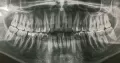

4 дня подряд ставили пломбы: стоят на верхней и нижней челюсти (напротив друг друга). Вчера были неприятные ощущения (не могла полностью закрыть рот, мешал кусочек пломбы), в стоматологии его убрали. Сегодня опять неприятно, но рот закрыть могу и челюстью двигать как раньше.

Это привыкание или всё-таки она будет продолжать мешать?

Привыкать к завышающей пломбе нельзя, Вы нанесете травму корневой системе и зубу в целом. Смыкание должно быть равномерным с обеих сторон.